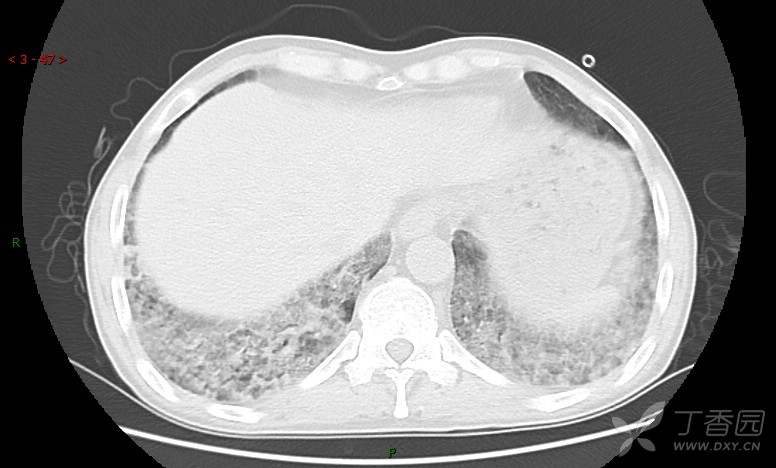

地图+铺路石征=PAP?那升高的CEA怎么说(病例3连发,附其他2例链接)

患者男,42岁,咳嗽半年余,加重伴憋喘2月余。

血清肿瘤相关抗原116.22U/ml↑(0--95);

癌胚抗原 61.96 ng/mL ↑ 0--5

神经特异性烯醇化酶 33.12 ng/ml ↑ 0--16.3

细胞角蛋白19片段测定 40.23 ng/ml ↑ ≤3.3